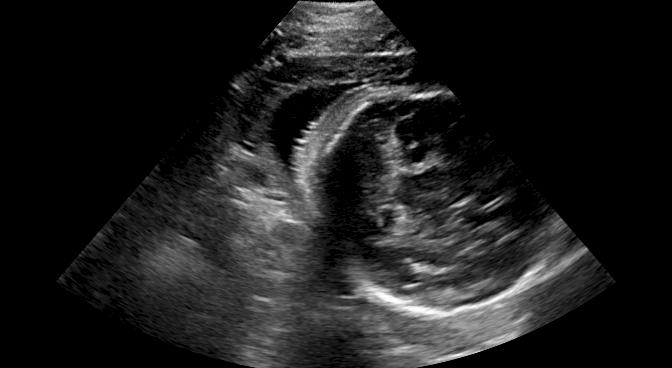

Fig. 6 compares the shadow confidence maps of the state-of-the-art methods and the proposed methods. RW and have the same parameters as used for Table I. The shadow confidence maps of the baseline, the proposed method and the proposedAG method are generated directly from input shadow images by confidence estimation networks. Overall, the proposed method and the proposedAG method achieve more visually reasonable shadow confidence estimation than the baseline and the state-of-the-art on different anatomical structures shown in Fig. 6. The proposed method and the proposedAG method are able to highlight multiple shadow regions while the RW algorithm shows limitations for most cases, especially for disjoint shadow regions.

Row I in Fig. 6 shows a fetal brain image from . The confidence estimation of shadow regions from the baseline, the proposed method and the proposedAG method are similarly accurate since we use fetal brain images to train the confidence estimation networks in these three methods. These outperform [16] and [22]. Rows (II-IV) in Fig. 6 show shadow confidence maps of non-brain anatomy from , including lips, abdominal and cardiac. The baseline failed on unseen data during inference. However, the proposed methods are able to generate accurate shadow confidence maps because of the generalized shadow features obtained by the shadow-seg module. Furthermore, the “Lips” example shows that our method is capable of detecting weaker shadow regions that have not been annotated in manual segmentation. This indicates that the confidence estimation network has learned general properties of shadow regions.